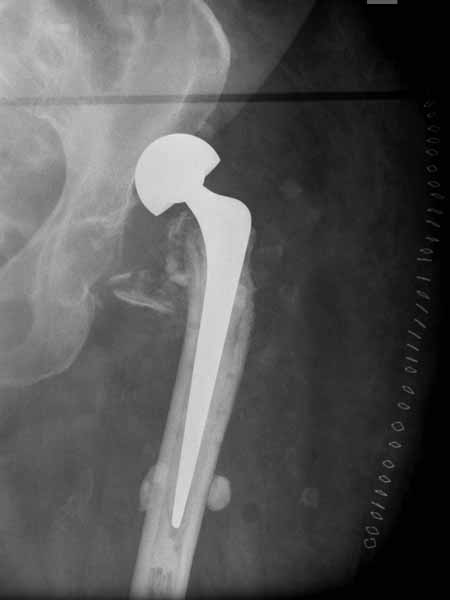

Сеньоры-пэры ревизировали гвоздем, шуруп поставили по той же дорожке, только поглубже. Да еще и bone graft не пожалели. "Результат" уже был через 2 дня.

Если сохранять головку - думаю надо было в валгусе фиксировать перелом гвоздем, или DCS, т.к. все-равно разрезали, чтоб достать DHS.

Бедная бабушка!

Неужели фиксация протеза бесцементная? Да и чашка не запрессована как надо.Грустно(

Эт -ж биполяр:)) Ножка цементная. Страйкеровский Exeter.1

биполярный эндопротез все же не лучший выбор для данной ситуации.судя по снимкам мышечные прикрепления на вертелах утрачены.Возможно здесь подошла бы более стабильная конструкция.Ваше мнение?

а куда делся фрагмент большого вертела? Очевидно,

Если среднеягодичная мышца не рефиксирована, то ничто не держит протез во впадине и это закономерный результат.

Третья операция-продолжения усилии “синьорами пэрами” по разрушению нормальной анатомии. Крест на головку! По видимому возраст позволяет биполярную конструкции, и при дефекте calcar пошли на обычный цементный. Ягодичные мышцы потеряли связь с вертелом, т.е. отсутствует верхний удержатель, и результат “a Big Screw Up!” Снимки вызывают головокружение!

Если хирурги не устали от своих “творчеств”, тогда можно ре-оперировать с calcar replacement stem, и собрать остаток ягодичных мышц. Глубина и отстутствие артроза позволяет применить любой, биполярный или тотальный, хотя принять решение можно после ревизии ацетабулума.